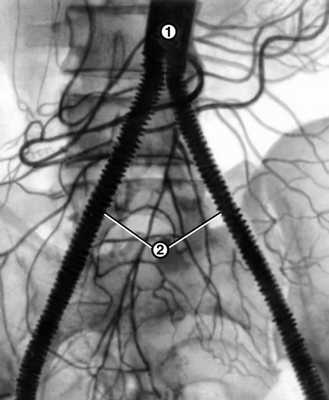

Показанием к реконструктивной операции на сосудах является ишемия конечностей IIБ, III и IV степени. Противопоказания — полная непроходимость артерий голени и бедренных артерий по данным ангиографического исследования, инфаркт миокарда, инсульт в сроки до 3 мес., сердечная недостаточность III стадии, цирроз печени, почечная недостаточность. При оперативном лечении Л.с. используют в основном два вида операции: резекцию сосудов с протезированием (рис. 3) и шунтирование. Резекцию аорты выполняют при ее окклюзиях и резком стенозе, шунтирование — чаще при сохранении проходимости подвздошных артерий (см. Кровеносные сосуды).

Рис. 3. Аортограмма больного с синдромом Лериша после резекции брюшной части аорты с бифуркационным протезированием: 1 — аорта; 2 — сосудистый протез, идущий от аорты к глубоким артериям бедер.